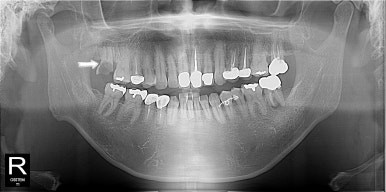

원래 발치하기로 했던 치아는 더 썩어서 부러져 있어고 좌측 아래 작은 어금니도 그동안 충치가 많이 진행되어 신경치료가 필요한 상황이었다.

무사히 비수면으로 신경치료도 마치고 크라운 치료까지 잘 받아주셨다.

그래도 아직 임플란트 수술까지는 무서워하시니 수술은 다시 수면치료

수술도 잘 끝나셨고 자주 보니 더 친해지고 해서 더 용기내서 잇몸이 많이 부어서 잇몸치료가 필요한데 비수면으로 진행해보자고 말씀드리고 당일 도포마취, 무통마취 내가 할 수 있는 조치는 다 해서 무사히 첫 번째, 두 번째 잇몸치료를 마쳤다...